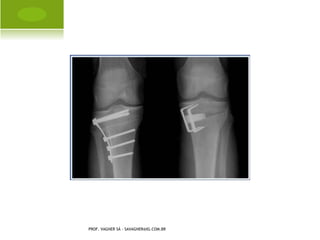

A RTROPLASTIA TOTAL

PROF. VAGNER SÁ - SAVAGNER@IG.COM.BR